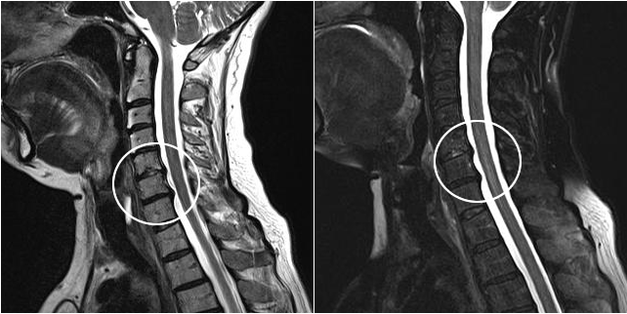

- Vascular-radicular stage.The fibrinous ring completely loses its shape.From this moment, hernias can form.X-rays are very informative.Subjective sensations of patients are pronounced (pain, sharp pain attacks, constant discomfort).Frequent muscle spasms appear and performance decreases significantly.If nerve fibers suffer, then the first signs of dysfunction of internal systems are inevitable;

Modern diagnostic methods include MRI and CT, which make it possible to more accurately examine the processes of destruction of cartilage and bone tissue.Also, using this technique is suitable for diagnosing hernias and other soft tissue defects near the source of the disease.